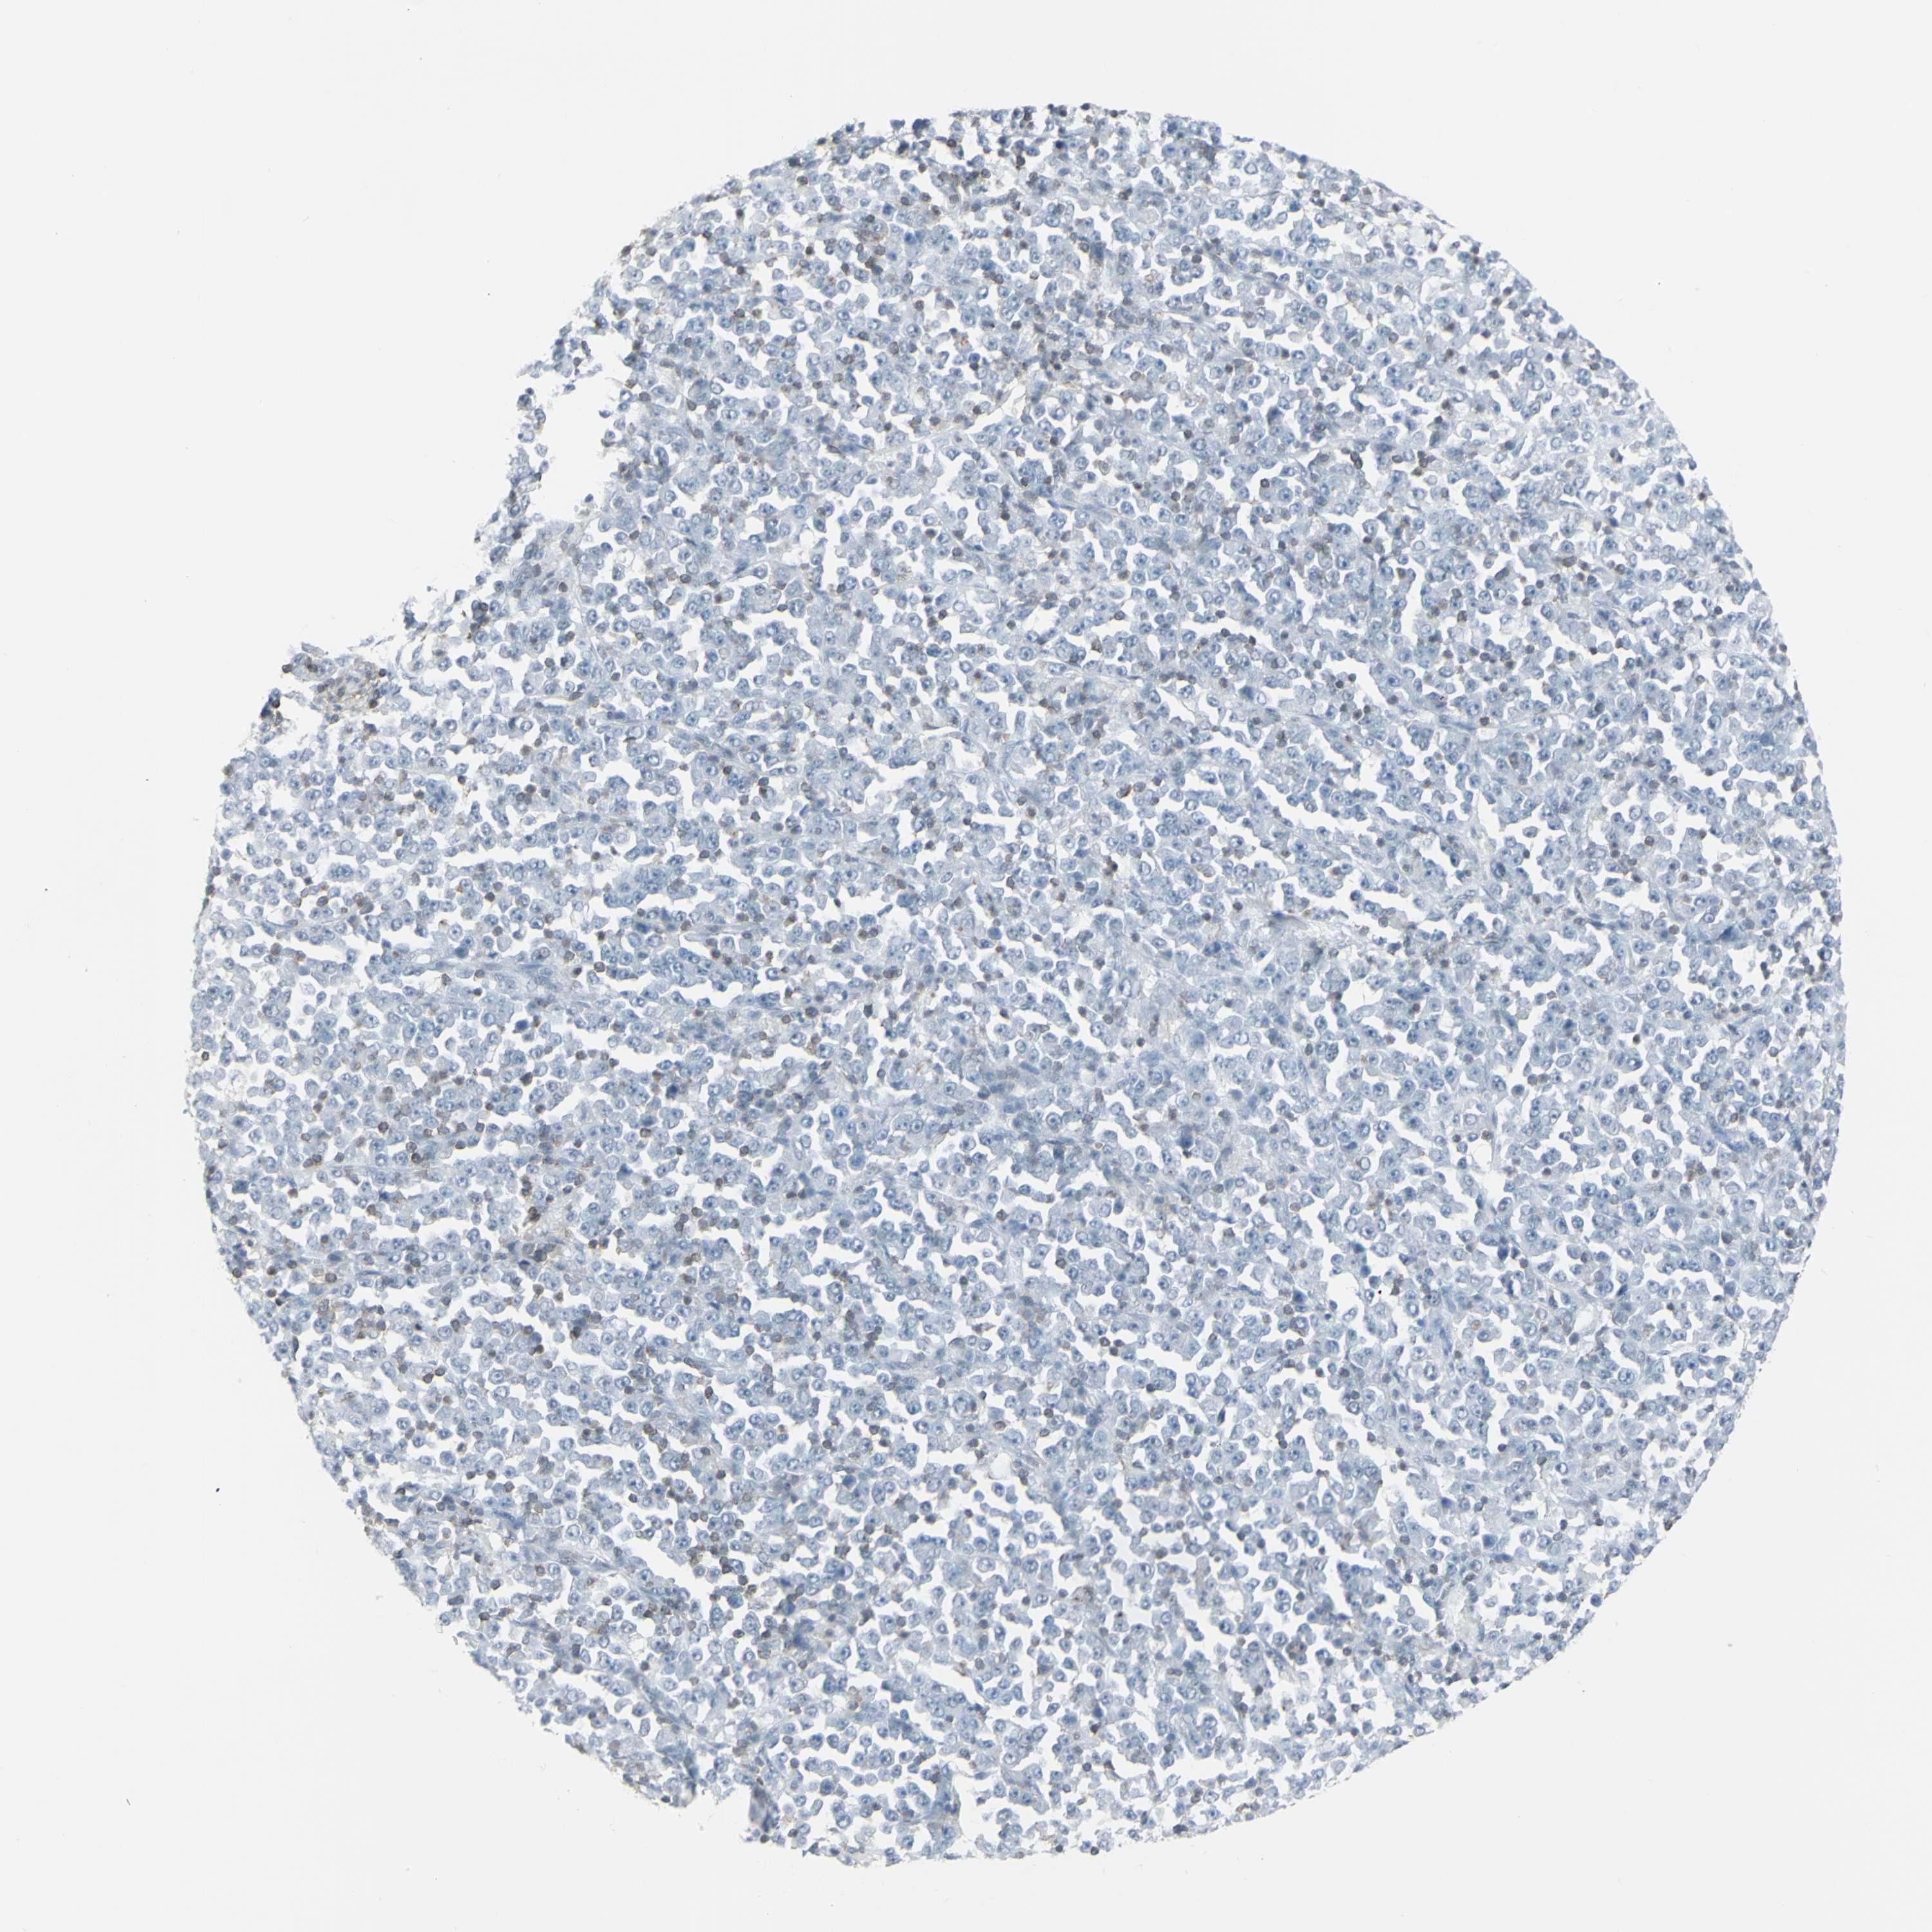

STOMACH CANCER - Protein expressioni

A mouse-over function shows sample information and annotation data. Click on an image to view it in a full screen mode. Samples can be filtered based on level of antibody staining by selecting one or several of the following categories: high, medium, low and not detected. The assay and annotation is described here.

Note that samples used for immunohistochemistry by the Human Protein Atlas do not correspond to samples in the TCGA dataset.

Antibody stainingi

Antibody staining in the annotated cell types in the current human tissue is reported as not detected, low, medium, or high, based on conventional immunohistochemistry profiling in selected tissues. This score is based on the combination of the staining intensity and fraction of stained cells.

Each image is clickable and will lead to virtual microscopy that enables deeper exploration of all samples and also displays staining intensity scores, fraction scores and subcellular localization as well as patient and tissue information for each sample.

Antibody HPA010964

Staining

High

Medium

Low

Not detected

Intensity

Strong

Moderate

Weak

Negative

Quantity

>75%

75%-25%

<25%

None

Location

Nuclear

Cytoplasmic/membranous

Cytoplasmic/membranous,nuclear

Adenocarcinoma, High grade